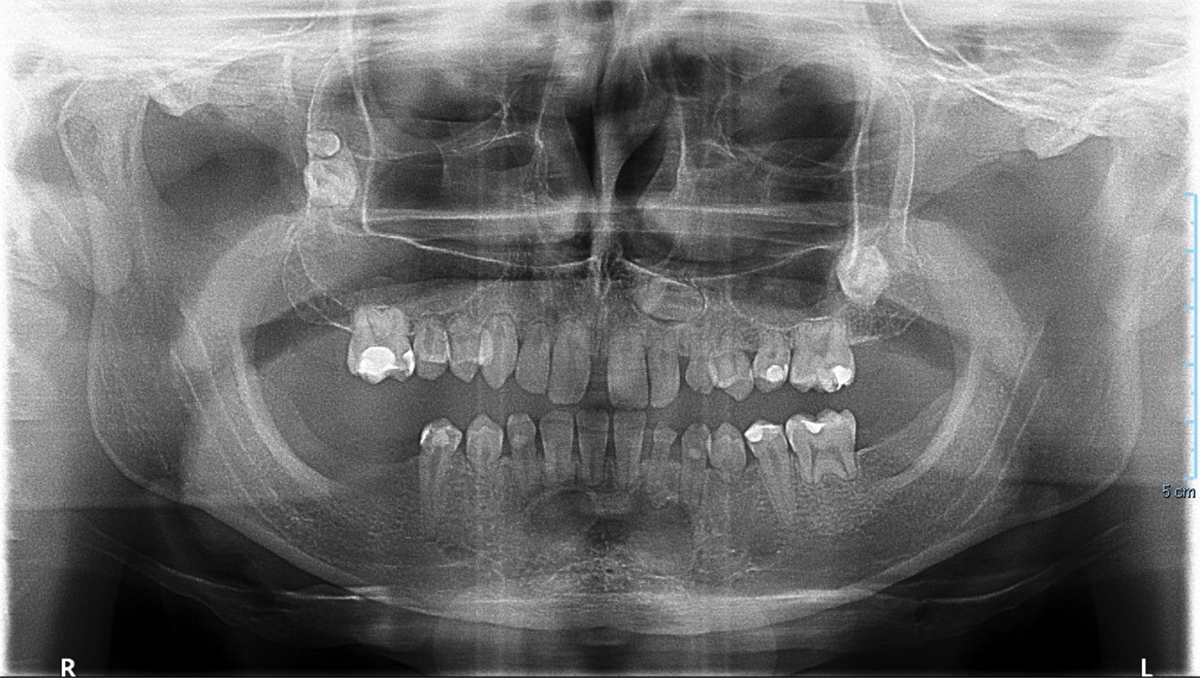

Panoramic radiograph (April 2024) of case 2 revealing agenesis, short roots, and impacted teeth.